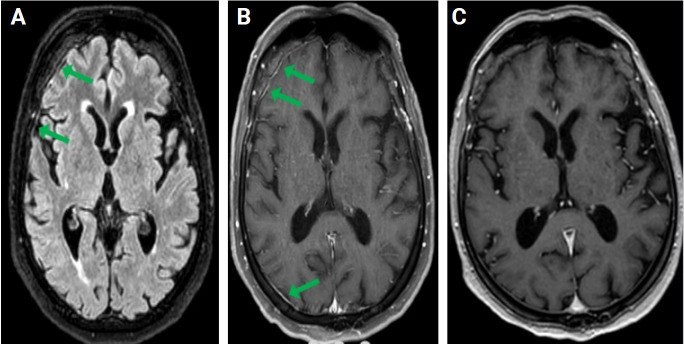

Immunoglobulin G4 (IgG4)-related disease is an immune-mediated, fibroinflammatory condition that causes multisystemic contrast enhancement and is predominantly observed in elderly male patients. The most prominent features of IgG4-related disease are systemic involvement affecting from two to six systems. In the central nervous system, these contrast enhancements are typically found in the meninges and orbit. This case study describes a 78-year-old female patient with persistent headaches and constant diarrhea who underwent treatment for IgG4-related disease. Despite two months of treatment with non-steroidal and opioid analgesics, the patient remained unresponsive and continued to experience diarrhea for 4 months. Brain magnetic resonance imaging revealed contrast enhancement in the leptomeningeal surfaces, and a biopsy of the gastrointestinal mucosa confirmed the diagnosis of IgG4-related disease, showing widespread plasma cell infiltration and IgG4 expression on plasma cells. The patient was initially treated with 1.0 g/day of pulse therapy for 5 days, followed by a maintenance dose of 1.0 mg/kg oral azathioprine. When azathioprine caused significant pancytopenia, rituximab therapy was initiated. The patient's headaches resolved completely, and the diarrheal attacks were controlled. This case highlights the importance of considering IgG4-related disease as a potential cause of headache or multiorgan symptoms in elderly patients with new-onset headache unresponsive to conventional analgesics. IgG4-related disease can often be effectively treated with steroids and monoclonal antibodies.